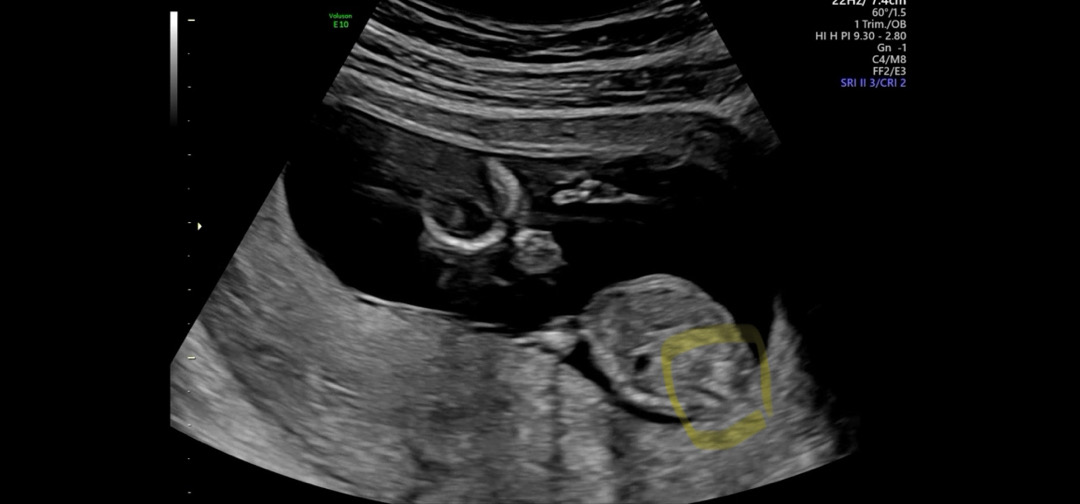

아는 언니가 이게 🌶️라고 ㅋㅋ 남자아이라고 하는데!!! 각도법은 딸 의견이 많았거든요 궁금하네요!!!

여기 이게 각도 나온 사진이에요!!

조심스럽게 아들 예상합니다~